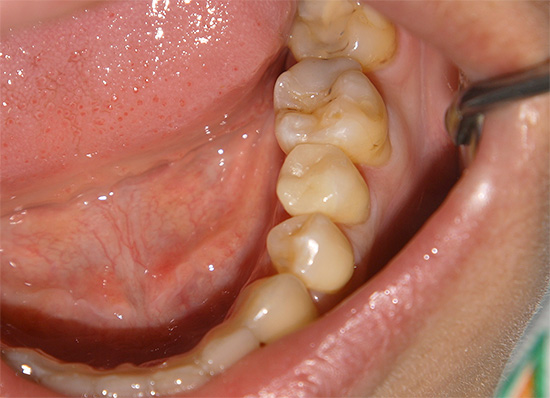

- La carie superficiale cronica porta alla formazione di una cavità nello smalto dei denti, ma senza danni alla dentina. Tale cavità non ha bordi sporgenti, è ampia, ben aperta, lo smalto stesso di solito si scurisce a causa della pigmentazione, ma mantiene una durezza relativamente elevata.

- La carie media cronica è caratterizzata da un'ampia cavità che colpisce la dentina. In questo corso, la cavità non ha ammorbidito la dentina, ma solo pigmentata dentina cariata. Il fondo è denso con lievi sporgenze e rugosità, che indica un processo lento nella fase di compensazione a causa della sostituzione della dentina.